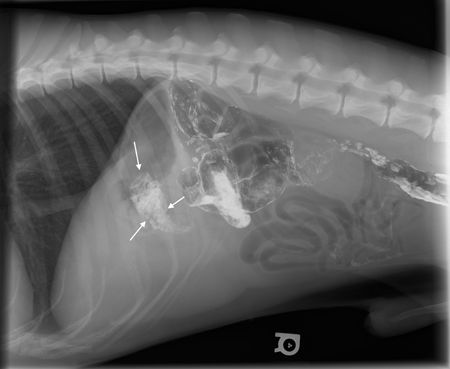

Gem 3: Contrast studies can still be done, but think of contrast medium like an overwhelming force-a little goes a long way. This may not make intuitive sense, as contrast medium is supposed to highlight abnormalities and is heavier than liquid so it settles, but remember that contrast medium is so opaque it will overpower and hide anything it covers. For example, consider a double-contrast cystogram. If you put too much iodinated contrast medium in the urinary bladder, you'll miss the stone. Also, for upper gastrointestinal tract examinations in stable patients, it's sometimes easier to see the foreign bodies four to six hours after administration of barium since the barium will stick to the foreign material after the rest of the barium clears (Figure 2). Just remember, if you're going to ultrasonographically examine the abdomen as well, do it before administering barium as this contrast medium will shadow and can be mistaken for a foreign body.

Figure 2A: This radiograph was obtained six hours after barium administration. Note all the barium is within the colon, except for a focal region in the stomach. This was a gastric foreign body (Vetrap) that was retained in the stomach.